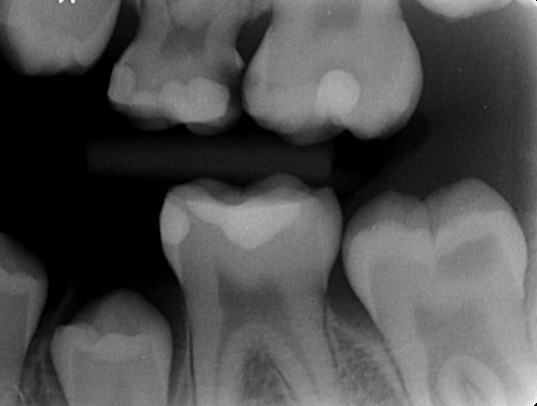

Caries opstår de steder på tænderne, hvor uforstyrret plak har fået lov til at sidde længst. Der kan ikke opstå caries i en ren tand eller på en ren tandoverflade.